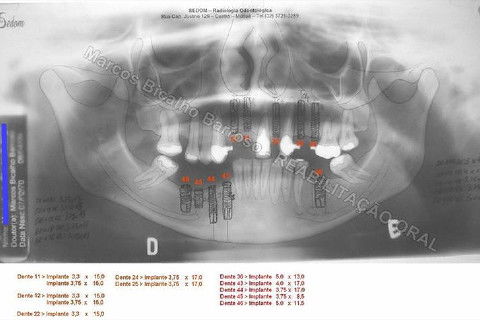

Paciente sexo feminino, 40 anos, queixava-se da situação da PPR superior, sem estabilidade, fraturas constantes nos dentes instalados. Sua vontade era resolver somente o problema da arcada superior, por questões financeiras. Logo no exame clínico inicial verifiquei a necessidade da reabiltiação inferior, pois este caso consistia em desarmonia oclusal severa, principalmente pela extrusão dos elementos 13,14 e 15 devido ausência de várias unidades inferiores. A proposta aceita pela paciente foi a instalação de 5 implantes na mandíbula + 5 implantes na maxila + tratamento endodôntico, osteoplastia e gengivoplastia nos dentes extruídos, incluindo núcleos metálicos e coroas em metalocerâmica (13,14,15). As coroas sobre implantes serão incialmente provisórias em resina fotopolimerizável e posteriormente metalocerâmica, de acordo com as possibilidades da paciente. Os procedimentos nos elementos extruídos serão apresentados em momento oportuno.